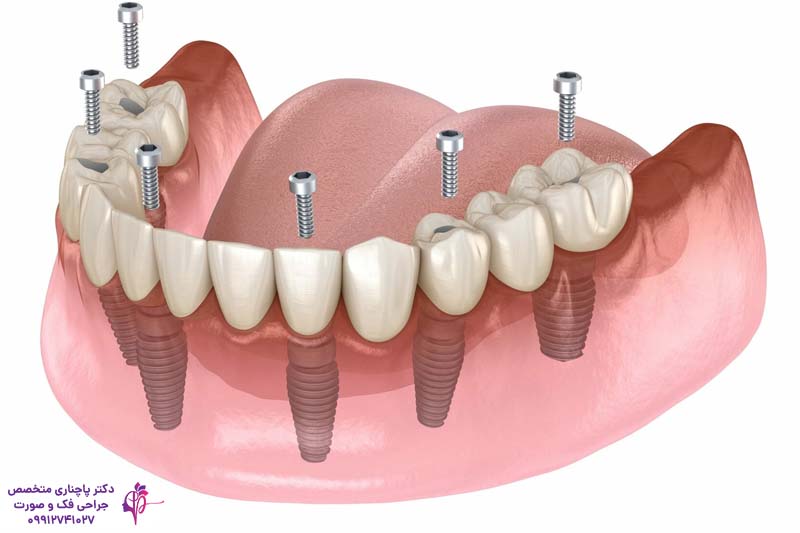

اوردنچر بر پایه ایمپلنت دندان، نسخه پیشرفتهتری از اوردنچر سنتی است که در آن به جای دندانهای طبیعی از ایمپلنتهای تیتانیومی به عنوان پایه استفاده میشود. ایمپلنتها پیچهای کوچکی هستند که در استخوان فک کاشته میشوند و مانند ریشههای طبیعی دندان عمل میکنند. بعد از کاشت پایهها پروتز اوردنچر روی آنها نصب میشود.

این روش برای بیمارانی که همه یا تعداد زیادی از دندانهای یک فک را از دست دادهاند ایدهآل است. ایمپلنتها با ادغام شدن با استخوان فک از تحلیل رفتن آن جلوگیری میکنند. در فک پایین معمولا دو ایمپلنت کافی است ولی برای فک بالا گاهی 4 تا 6 پایه استفاده میکنند. بعد از کاشت پایهها 3 تا 6 ماه طول میکشد تا پایه با استخوان ادغام شود و بعد از آن پروتزی که با دقت در آزمایشگاه ساخته شده روی آن نصب میشود. این ترکیب پایه و پروتز اوردنچر را به یک گزینه عالی تبدیل کرده که هم محکم است و هم بیمار میتواند مدلهای متحرک را برای تمیز کردن جدا کند.